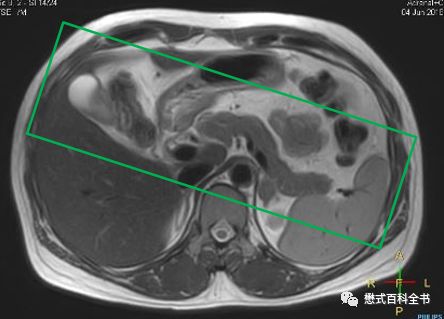

图17:MRCP的定位

图18:MRCP扫描角度一

如上图所示,第一种扫描角度,是在3D冠状位扫描的时候,在横轴位上,扫描角度平行于主胰管走形。使用该定位角度显示胰管及胆总管下段可能比较好,但是对于肝内胆管,则由于角度问题,不能最好的反映左、右肝管汇合成肝总管的情况。